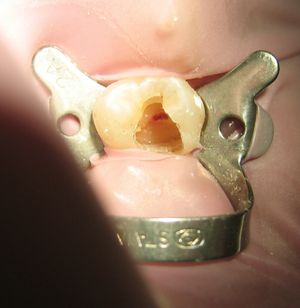

치수가 완전히 괴사한 경우에는 환자가 통증을 느끼지 못하므로 마취 과정을 생략할 수도 있다. 마취를 할 경우에는 공포심을 느끼는 환자를 위해 주사 전 마취 크림으로 표면 마취를 미리 해주는 것이 좋다. 또한 마취액을 주사할 때는 체온과 유사한 온도의 마취액을 가급적 천천히 일정한 속도로 주입하면 환자의 통증을 줄여줄 수 있다. 타액의 방습에는 솜말이(cotton roll)나 러버댐(Rubber dam)을 사용한다.

러버댐(rubber dam) 장착 가능 여부를 확인한다. 또한 교합면을 삭제해 근관 치료 과정 중 씹는 교합압 또는 저작압에 의해 발생할 수 있는 교합 외상을 피하고, 치아의 파절을 방지한다. 자연 치질의 벽이 부적절할 경우엔 인위적으로 벽을 형성해주고, 근관장 측정 시엔 일정한 기준점을 유지한다.

방사선 사진에서 치수강의 위치와 형태를 확인한 후 고속 핸드피스(high speed handpiece)에 라운드 버(round bur)나 #245, #330 버(bur) 등을 이용해 와동을 형성(cavity preparation)하고 치수강 내에 치수가 존재하는 경우 라운드 버(round bur)나 엔더단틱 스푼 엑스케베이터(endodontic spoon excavator)로 제거한다. 이때 치수실저(chamber floor)와 벽을 삭제하지 않도록 주의한다. 스무스 브로치(Smooth broach)나 근관 탐침을 이용해 근관의 입구를 찾고, 필요에 따라 추가적인 치과용 국소마취로 동통을 조절한다.